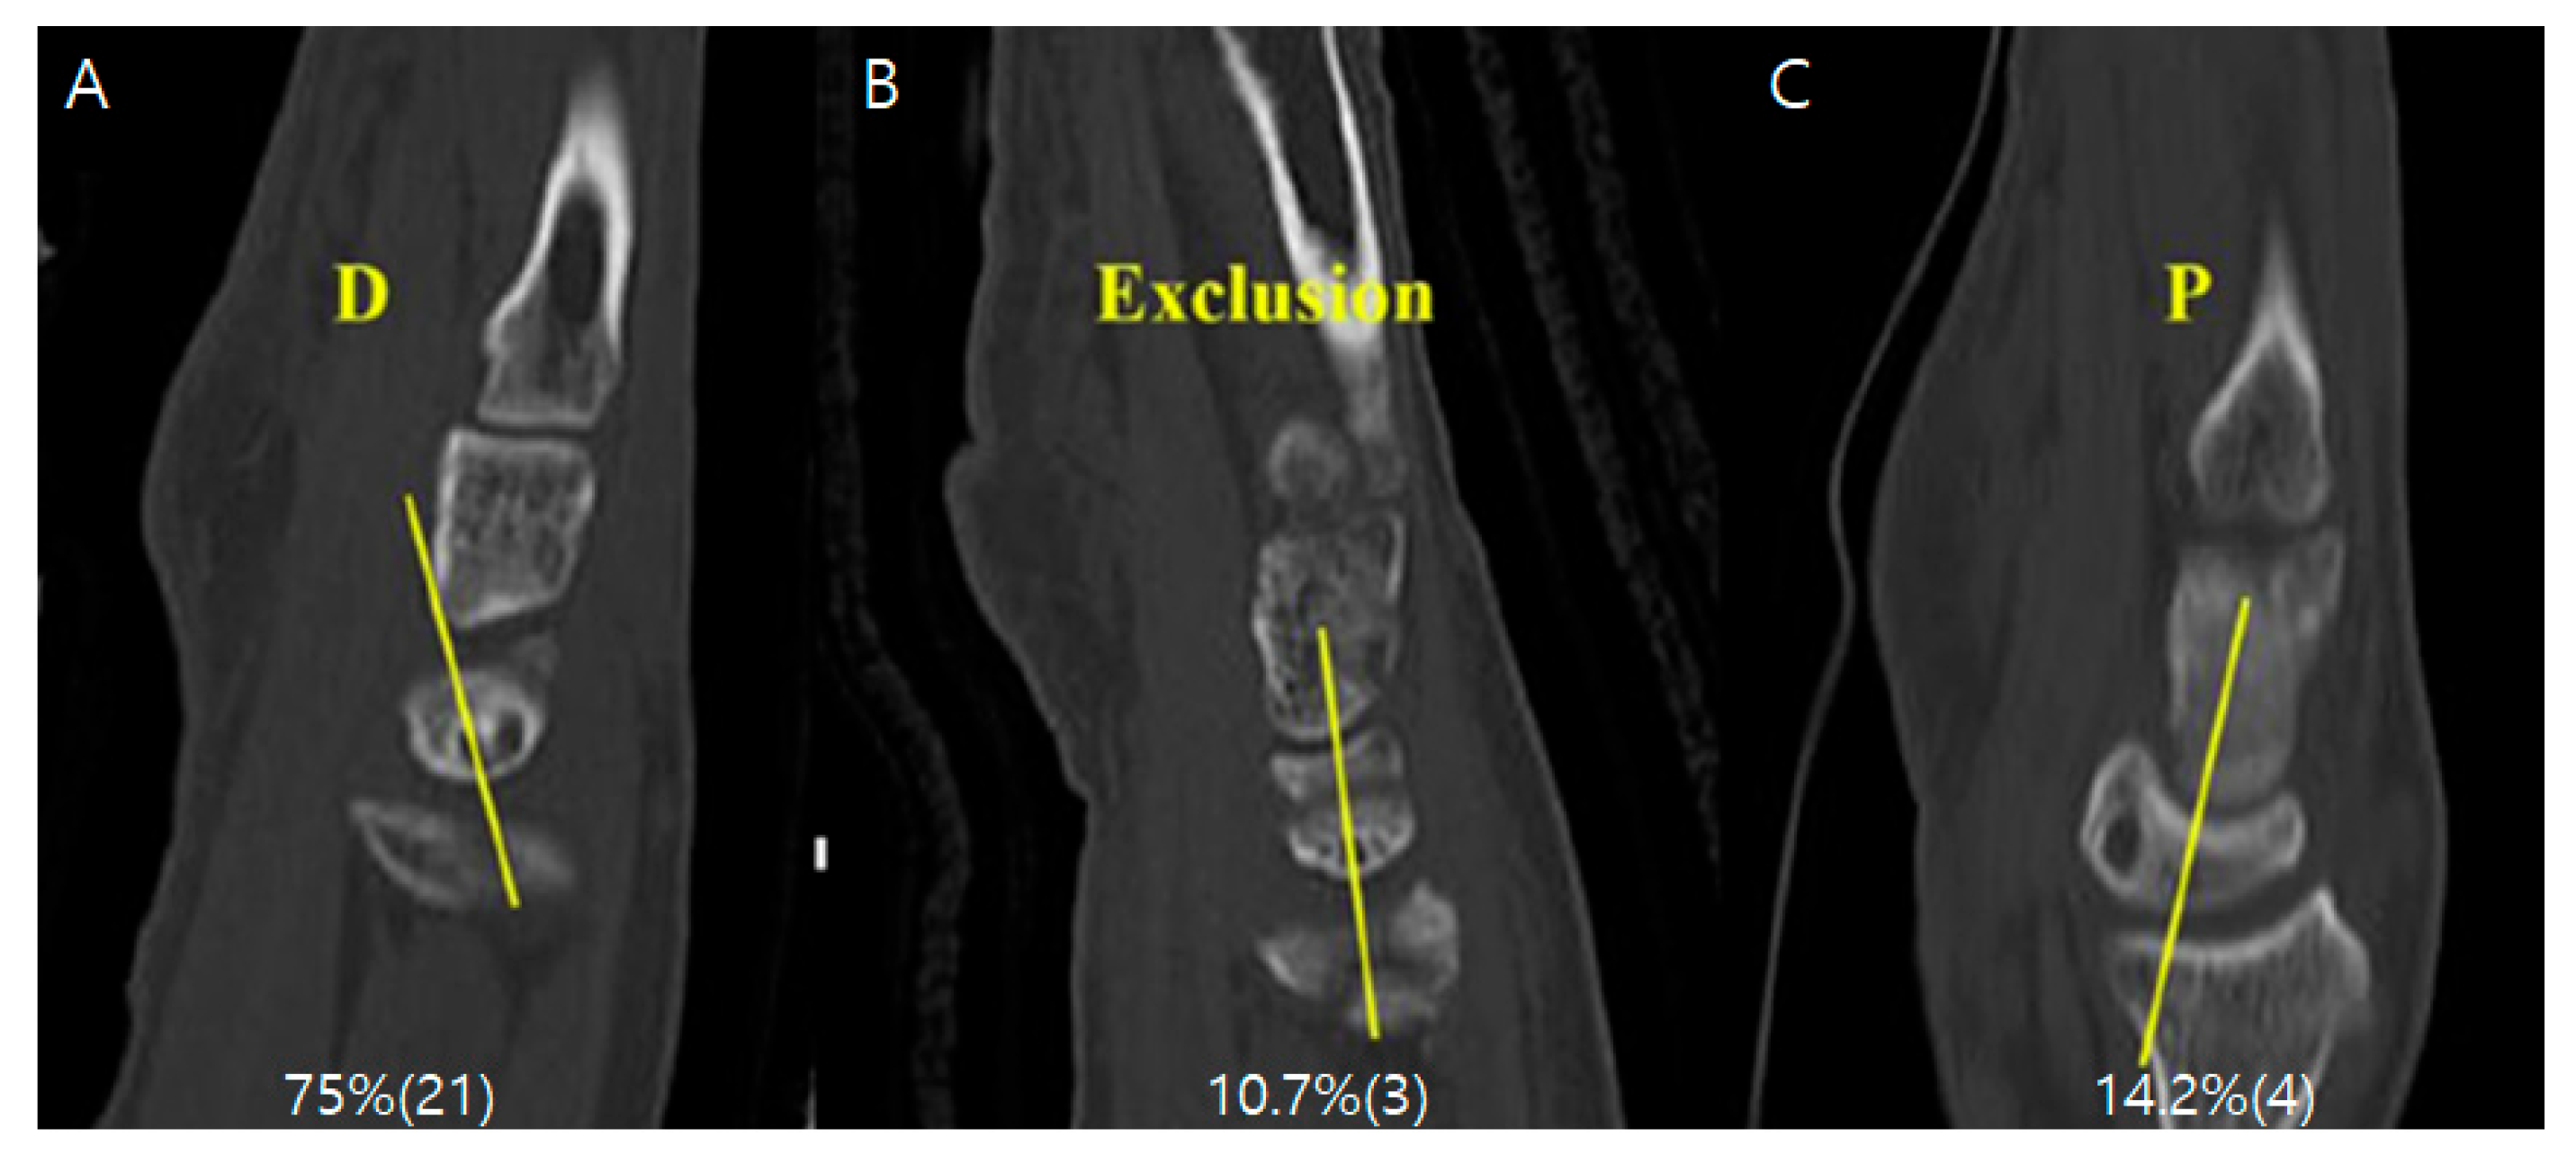

Radiologic Evaluation: Radiologic parameters, specifically ulnar variance and ulnolunate distance, were measured immediately postoperatively and at the final follow-up. Measurements were performed twice by two orthopaedic residents independently, and the mean values were used for analysis. Ulnar variance was measured on standard PA wrist radiographs (taken with the shoulder abducted 90°, elbow flexed 90°, and forearm in neutral rotation) using the method of perpendiculars. To compensate for potential measurement errors in ulnar variance, we also measured the ulnolunate distance, defined as the shortest distance between the lunate ulnar corner and the most convex point of the ulnar head (Figure 1 and Figure 2). Additionally, the location of the lunate cyst was evaluated using preoperative computed tomography (CT). Preoperative CT was obtained as part of routine clinical care when intra-articular involvement or complex fracture morphology required further assessment for surgical planning, and it was not performed solely for research purposes. CT acquisition followed our institutional clinical protocol, and no additional imaging was requested specifically for this retrospective study. Cysts were classified as dorsal or palmar based on sagittal CT images. Cysts that could not be clearly localized to either side were categorized as “unclassified” (Figure 3).

Figure 3. Location-specific distribution of lunate subchondral cyst. (A) Dorsal cyst on sagittal CT. (B) Unclassified cyst when localization was indeterminate. (C) Palmar cyst on sagittal CT.

Surgeries 07 00039 g003